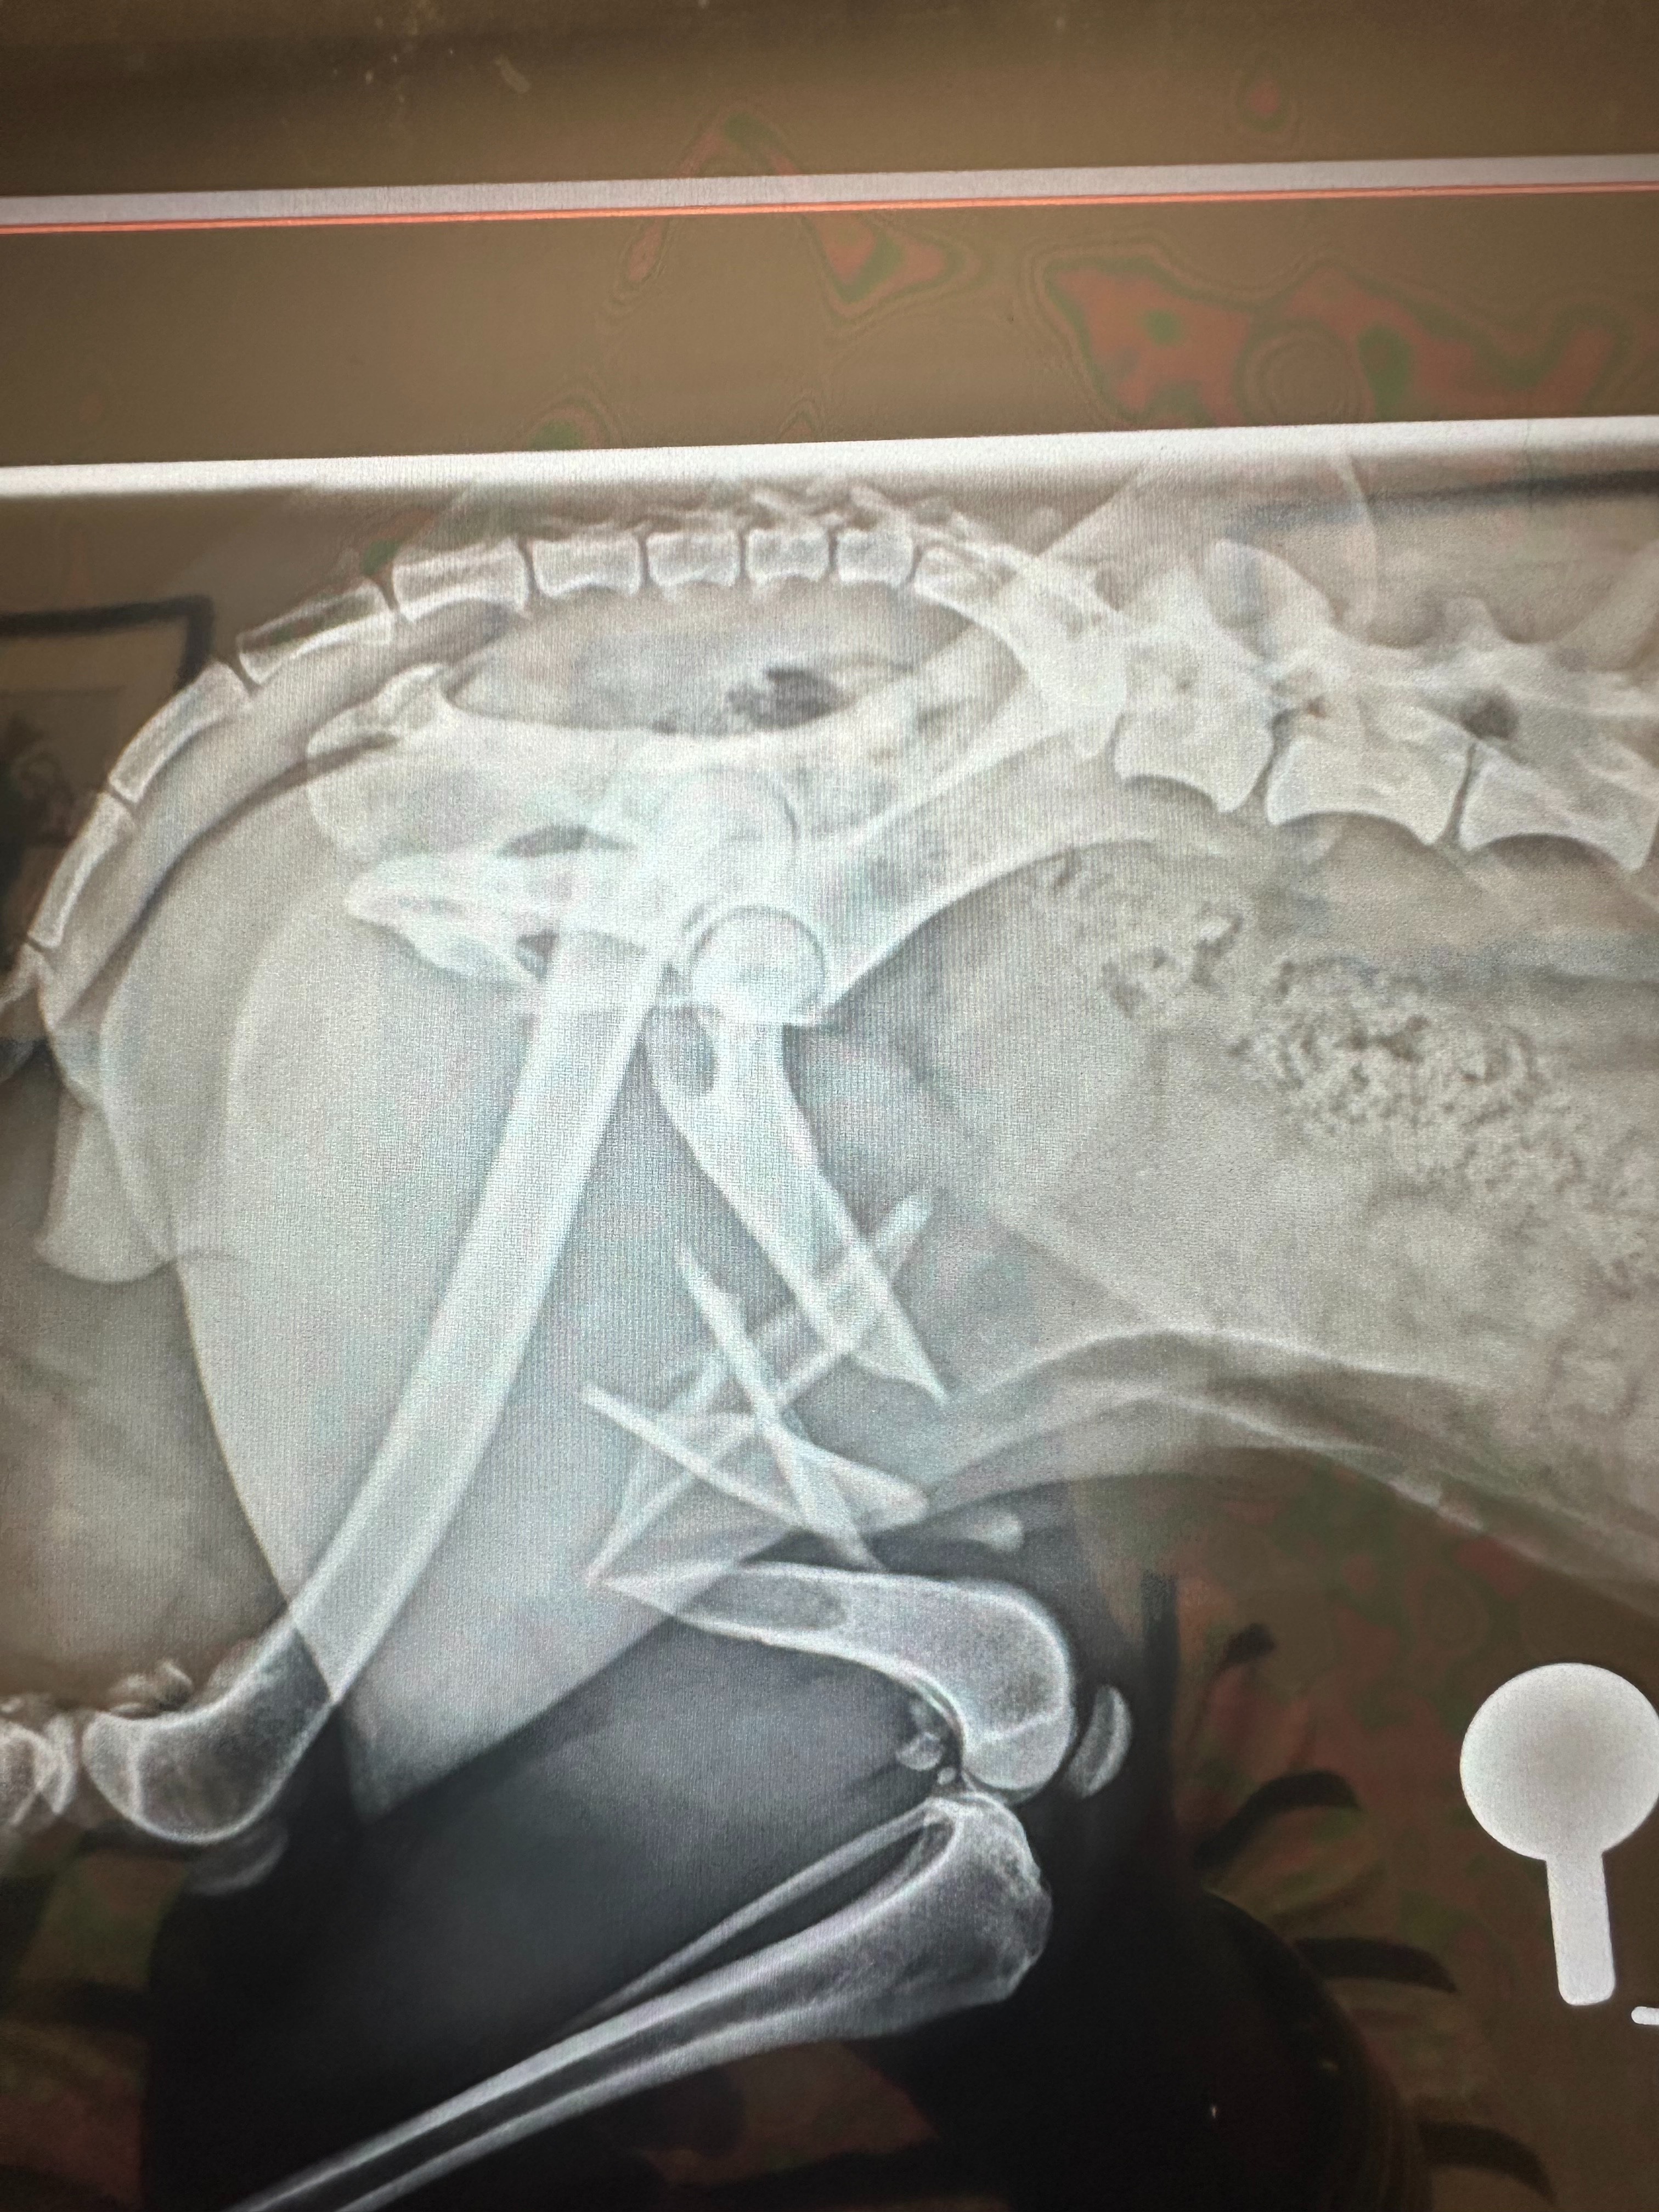

Lox had been completely shaved, losing her signature cords — her beautiful “lox.” But even more devastating, her leg was broken in six places. The initial vet attempted surgery, but due to the severity of her injuries, they were forced to amputate her leg to save her life.